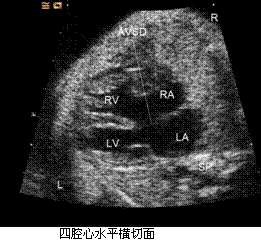

孕妇,36岁,孕2产1孕25周,无特殊病史,实验室检查无明显异常,心脏超声所见如下图。 GJ33_22_29.gifGJ33_22_29_1.gif (L-左侧,R-右侧,LA-左心房,RA-右心房,LV-左心室,RV-右心室,AAO-升主动脉,MPA-主肺动脉,SP-脊柱)